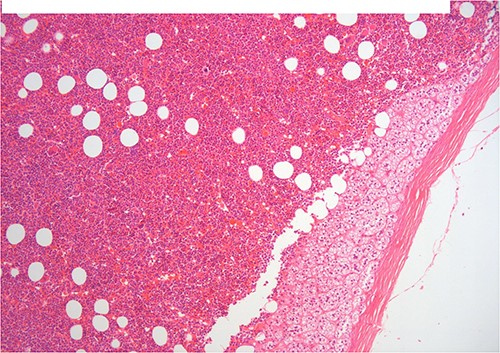

A 50-year-old woman was referred for surgical resection of a large right adrenal mass, which was incidentally found in an ultrasound scan performed for vague abdominal symptoms. Subsequently an abdominal MRI scan depicted a 16 × 15 × 6 cm right adrenal mass with characteristics suggestive of a myelolipoma, without evidence of vascular or periadrenal organ invasion (Figs 1 and 2). The patient underwent a comprehensive hormonal serum testing that confirmed a nonfunctioning adrenal mass. Because of the size of the lesion, an open operative approach was selected. Through a supraumbilical midline incision the mass was carefully dissected from the surrounding structures. It was adherent to the right kidney, the liver and the inferior vena cava without, however, compressing it. The harmonic scalper was used and clipping of the adrenal vasculature as appropriate. Intraoperatively, there was no adverse event. The specimen was removed intact and was sent for histological examination (Fig. 3). A silastic corrugated drain was inserted before closure of the laparotomy. The patient’s postoperative course was unremarkable and she was discharged on the third postoperative day. Histopathology revealed a lesion consisting predominantly of fatty tissue containing all types of hematopoietic stem cells and confirmed the diagnosis of myelolipoma (Figs 4 and 5).

On histopathologic examination, myelolipomas are predominantly composed of mature adipose tissue with interspersed hematopoietic tissue components. These fatty elements and hematopoietic areas may be clearly separated, or they are often intermixed.